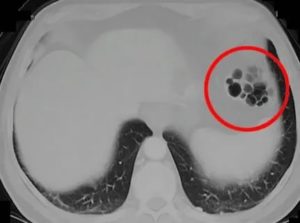

Пневматоз кишечника с образованием газовых пузырьков

По количеству различают единичные и множественные газовые кисты. Множественные бывают чаще, по внешнему виду они напоминают виноградную гроздь.

- обзорная рентгенография брюшной полости. Она определяет газовые пузыри разных размеров, размещенные цепочкой. Для пневматизированного кишечника характерно присутствие в раздутых кишечных петлях двойных кольцевидных теней;

- ирригоскопия. Она определяет лишний газ в увеличенных петлях толстого кишечника в виде нескольких рядом расположенных округлых теней, разделенных стенкой. В процессе исследования можно найти участки уменьшения просвета, аномальные новообразования, изъязвления трубки кишечника;

- колоноскопия. Эндоскопический метод дает возможность визуализировать пузырьки газа, оценить объемы поражения и состояние слизистой ЖКТ. Когда требуется, для гистологического анализа проводят биопсию участка кишки.